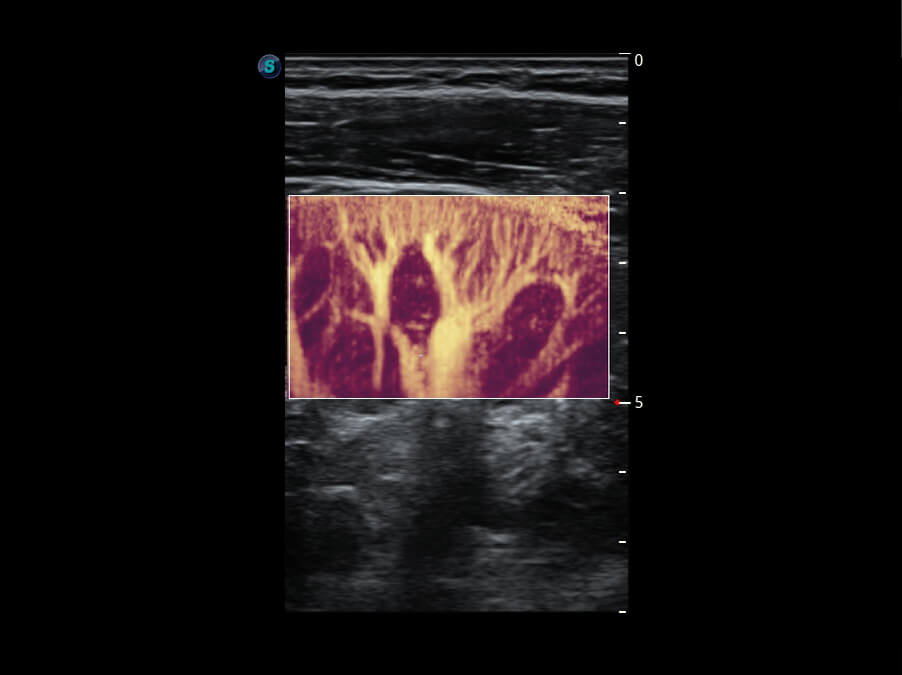

Micro F 显微血流成像 明察秋毫

• 新型复合材料探头( 12L-A )